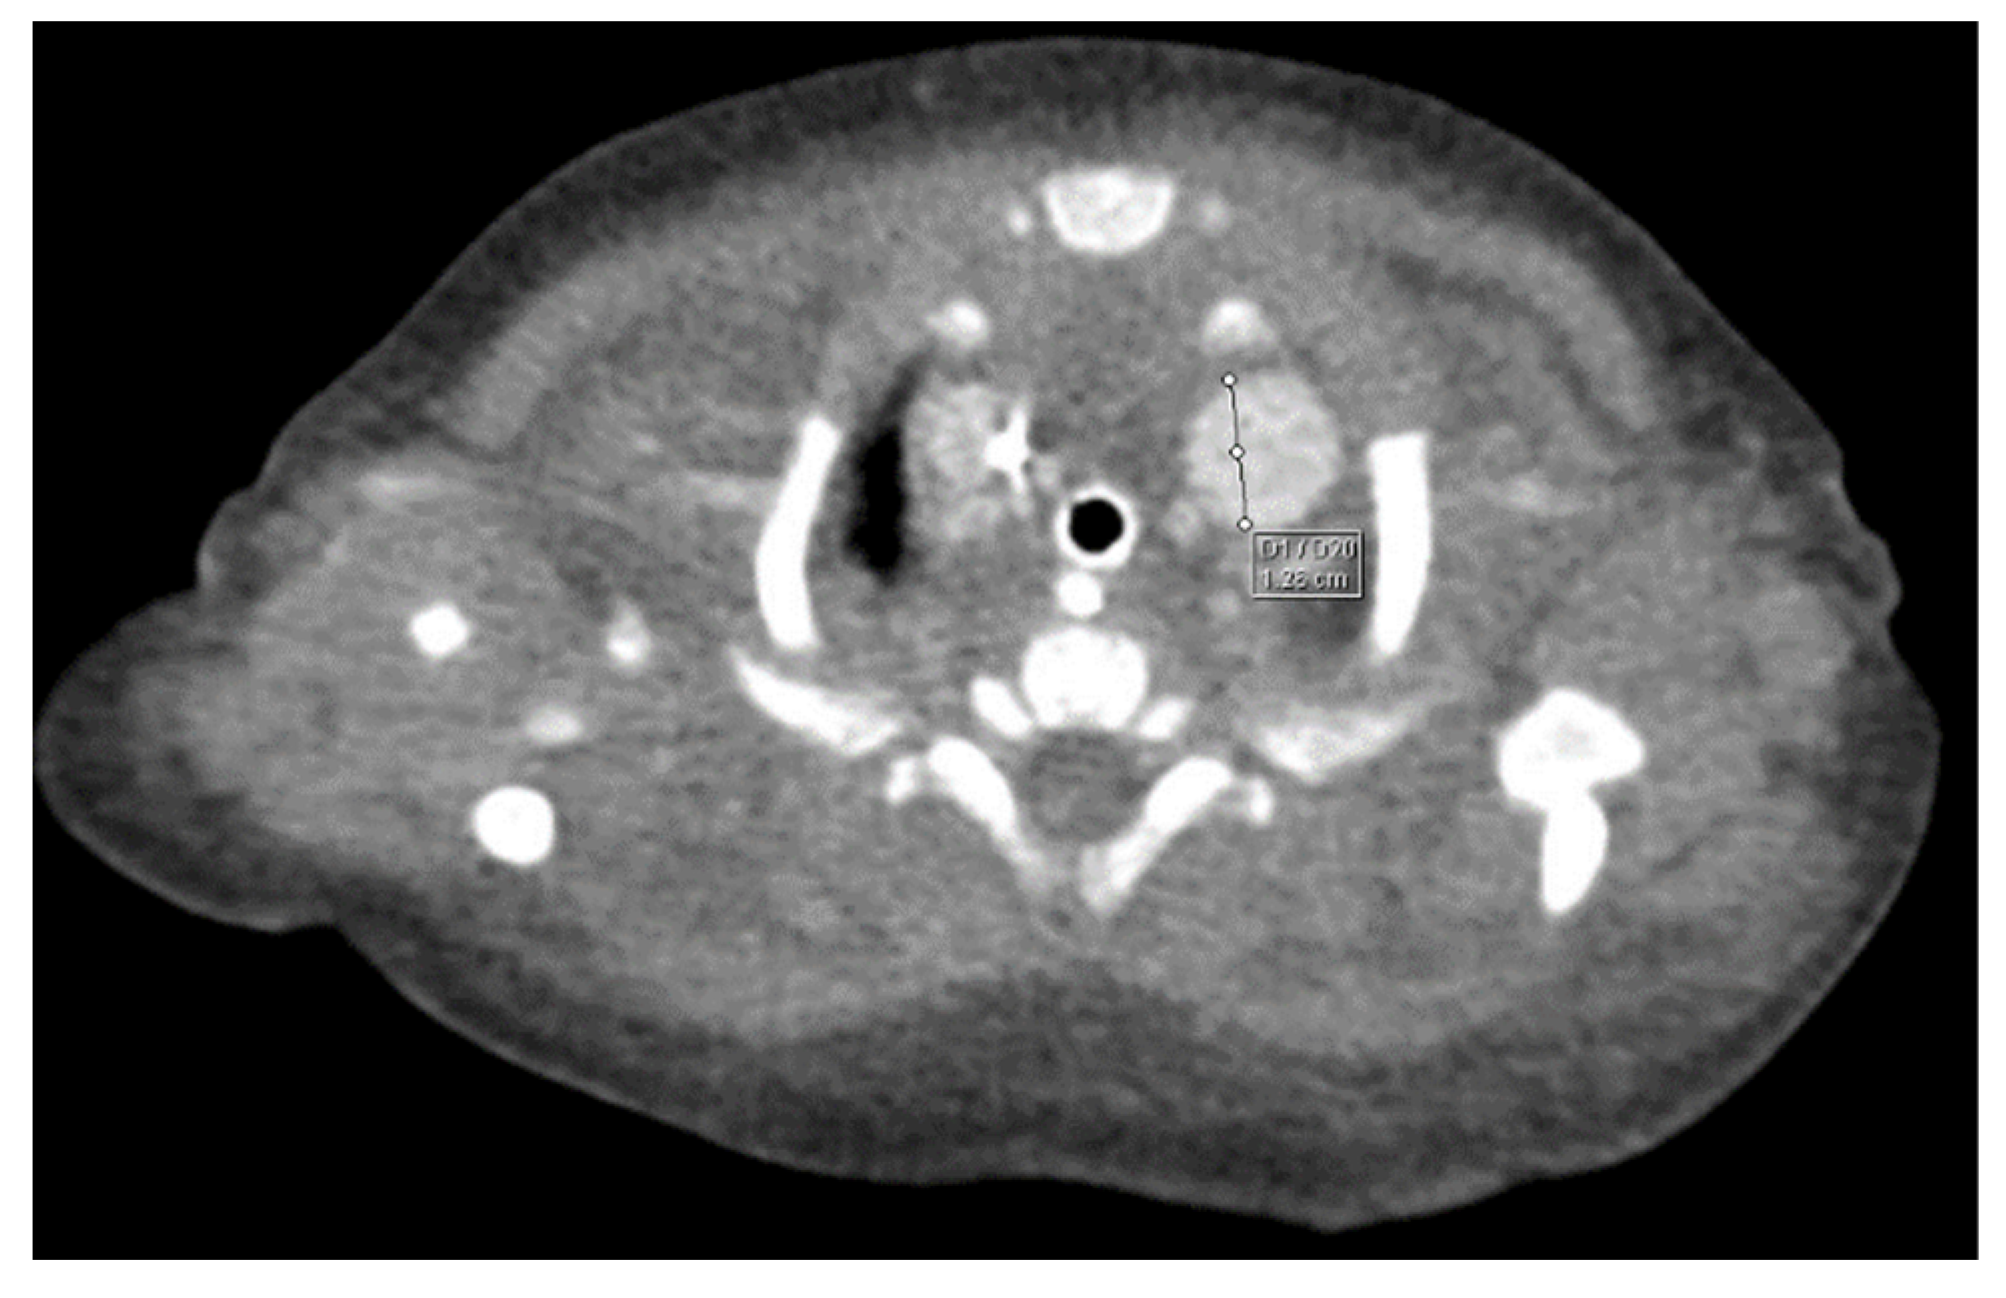

Through thoracic CT, we found SVC with a diameter of 15 mm (Figure 1), a venous collector with a 12 mm in diameter connected to the SVC and identified at the level of a plane passing through the middle of the left superior pulmonary lobe (Figure 2). The venous structure continues superiorly with the left brachiocephalic venous trunk, which was dilated up to 12 mm (Figure 3) and inferiorly with a left pulmonary vein. The pulmonary trunk appeared shorter, with a diameter of 6 mm, right pulmonary artery = 5.4 mm and left pulmonary artery = 5.6 mm (Figure 4 and Figure 5). We have identified traits of pulmonary consolidation (Figure 6).

Figure 3.

Venous brachiocephalic trunk.